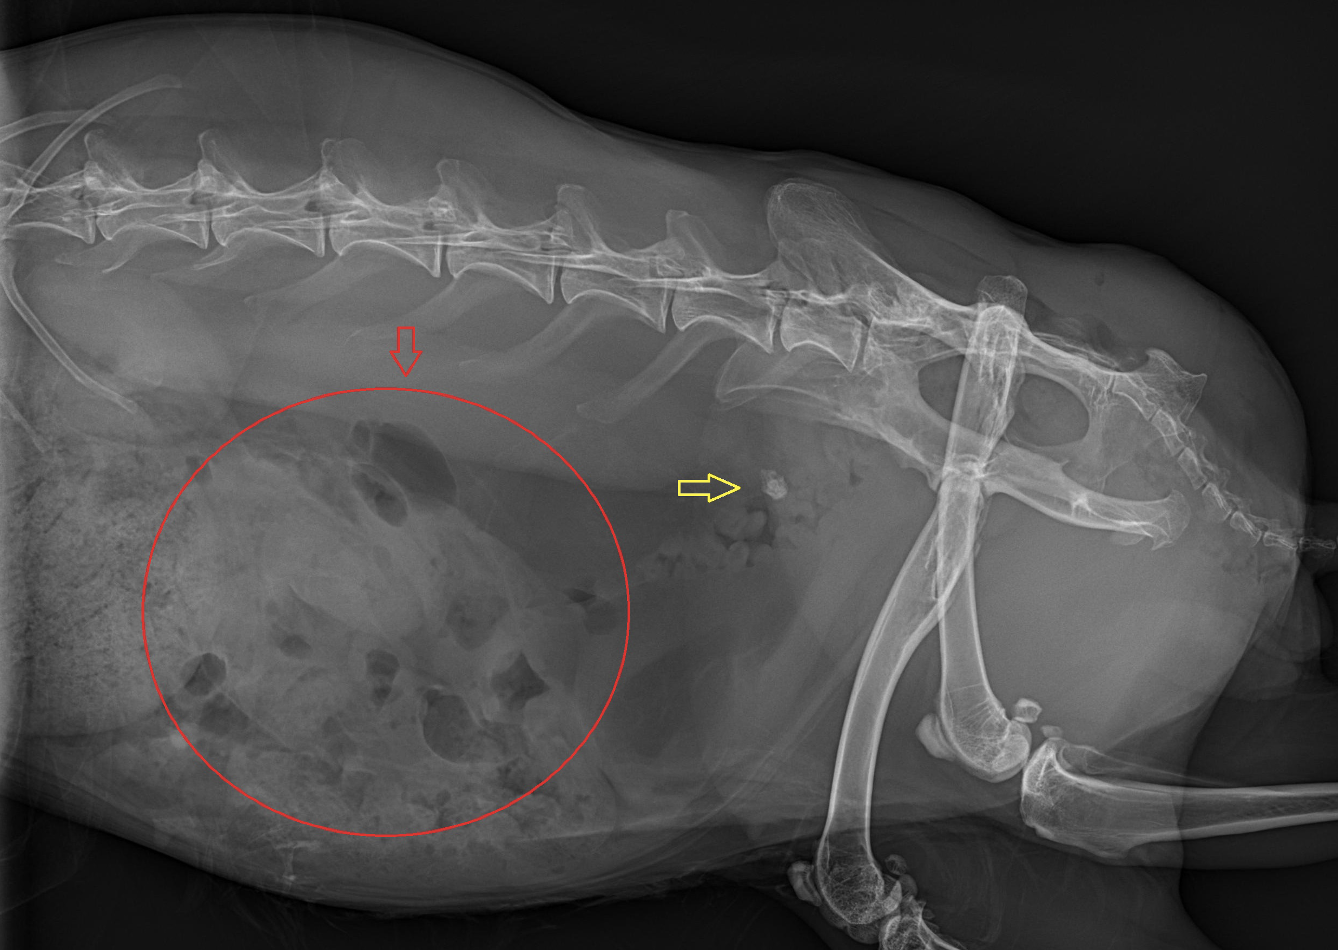

Die Röntgenuntersuchung zeigte eine weichteildichte Masse im rechten mittleren Abdomen sowie eine radiodichte Struktur dorsal der Harnblase. Die Sonographie ergab eine deutlich veränderte rechte Niere mit hochgradiger Hydronephrose sowie eine ausgeprägte Peritonealreaktion. Der rechte Ureter war stark dilatiert mit einer schallschattenbildenden Struktur kurz vor der Einmündung in die Harnblase. Die linke Niere sowie der linke Ureter waren sonographisch unauffällig. Auf Basis dieser Befunde wurde die Diagnose einer hochgradigen rechtsseitigen Hydronephrose sekundär zu einer Ureterolithiasis gestellt.